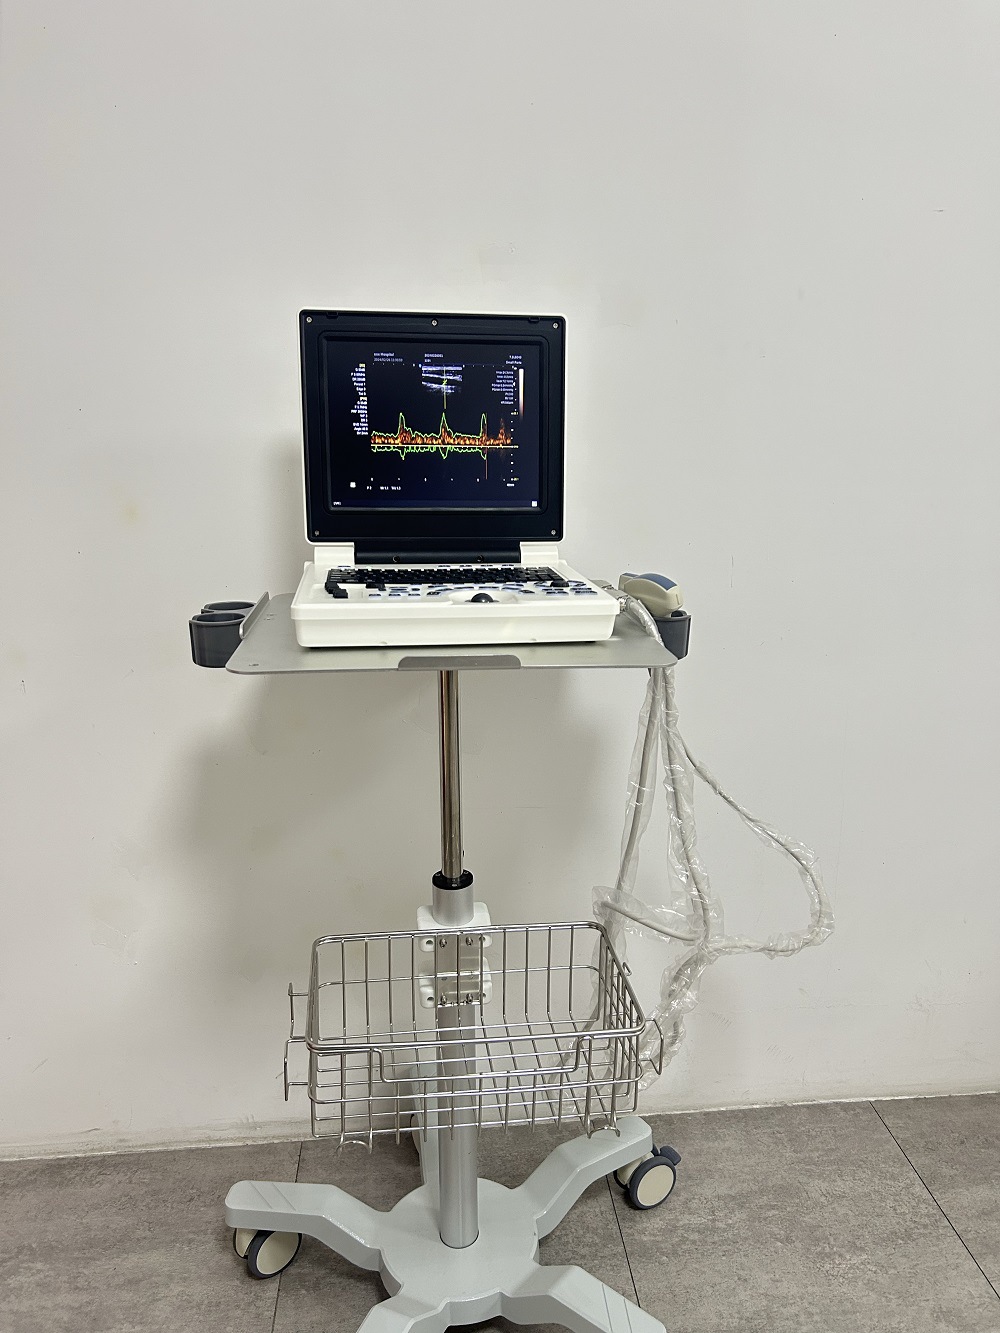

Портативный ветеринарный ультразвуковой диагностический прибор с высокой четкостью изображения, трансграничная английская версия, ультразвуковая диагностика животных

Портативный ультразвуковой аппарат Animal B; Выпуклый массивный зонд; Линейный зонд; Слегка выпуклый зонд; ректальный зонд